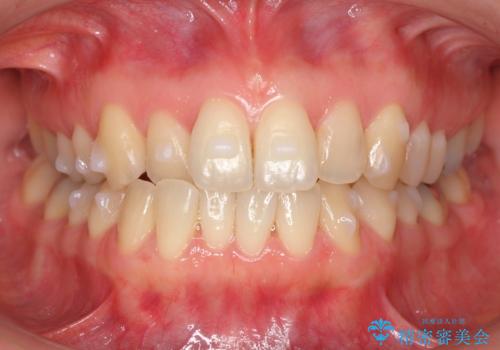

上の前歯が一部引っ込んでいる 下のがたがた マウスピース矯正

- 前歯2本が後ろに引っ込んでいる状態でした。

マウスピースで歯を抜かずに矯正しました。

左上4番は、虫歯治療をして、セラミッククラウンで修復しています。